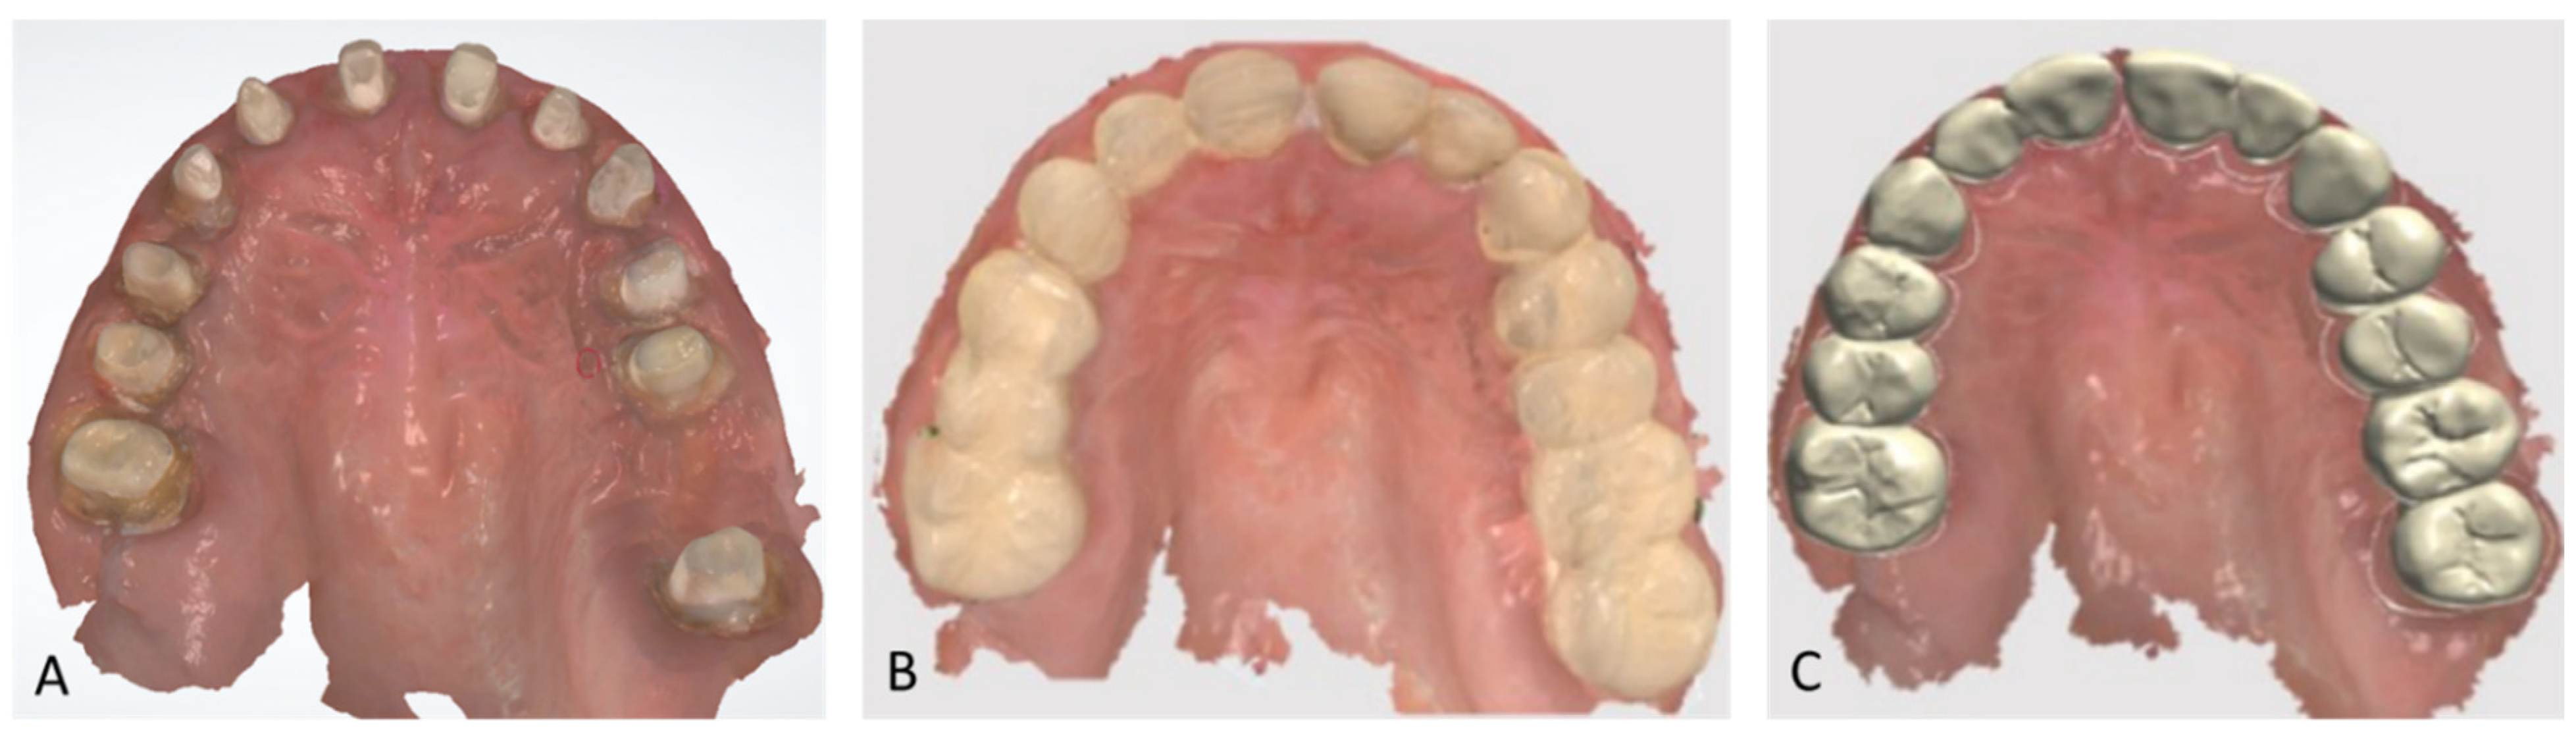

2.4.1. Step 1: Diagnostic Set-Up and Provisional Prosthesis

2.4.3. Step 3: Definitive Prosthetic Rehabilitation